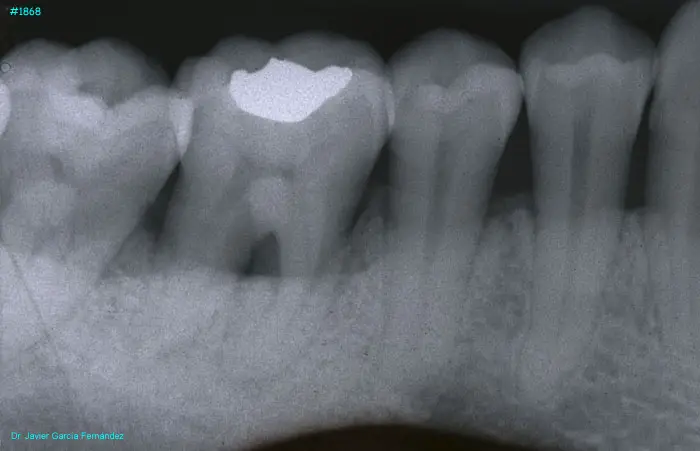

image 19